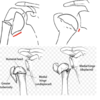

What is the Mayo classification of olecranon fractures?

[JAAOS 2013;21:149-160]

- Type I = undisplaced

- Type II = displaced but stable

- Type III = displaced but unstable

***Note: each group is subdivided into noncomminuted (A) or comminuted (B)

What is the Schatzker classification for olecranon fractures?

[JAAOS 2013;21:149-160]

- Type A = simple transverse

- Type B = transverse with central articular surface impaction

- Type C = simple oblique

- Type D = comminuted

- Type E = oblique fractures distal to the mid-sigmoid notch

* ‘Oblique distal’ to the greater sigmoid notch - Type F = combined olecranon and radial head fracture

* Often with MCL tear

What is the PUDA angle?

[JAAOS 2013;21:149-160]

PUDA = proximal ulna dorsal angulation

- The average PUDA is 6° measured 5cm distal to the tip of the olecranon

- Increased PUDA associated with decreased terminal elbow extension

What is the angulation of the proximal ulna in the coronal plane?

[JAAOS 2013;21:149-160]

Mean varus angulation of 14°+/-4°

- Measured between the axis of the olecranon and axis of the ulna midshaft